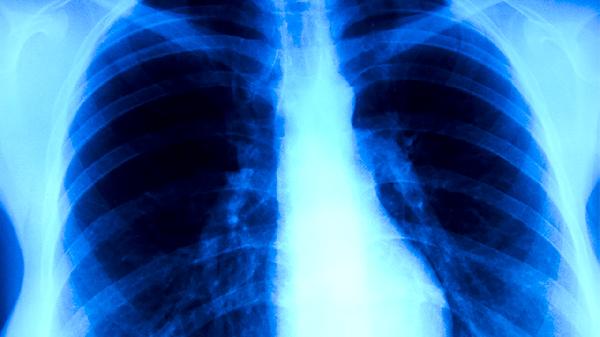

預(yù)防肺結(jié)核復(fù)發(fā)在飲食方面需要注意什么

預(yù)防肺結(jié)核復(fù)發(fā)需注意均衡飲食,適量補(bǔ)充優(yōu)質(zhì)蛋白、維生素及礦物質(zhì),避免辛辣刺激食物。主要有保證優(yōu)質(zhì)蛋白攝入、補(bǔ)充維生素A和D、增加鐵鋅等礦物質(zhì)、控制脂肪攝入、戒煙限酒等措施。